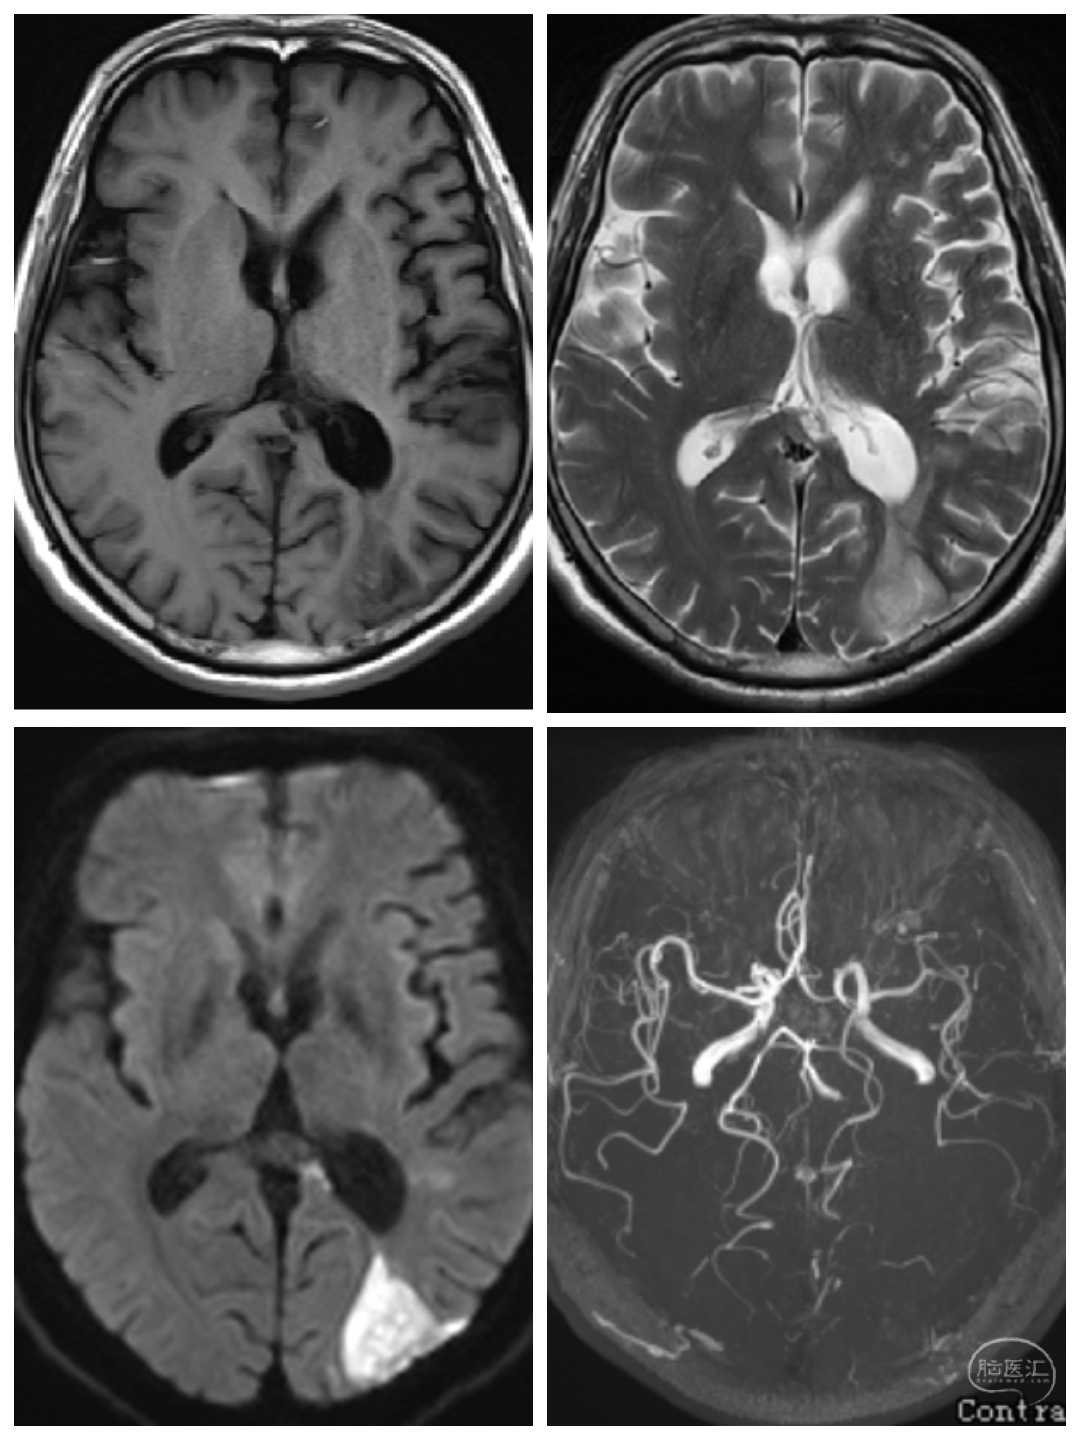

袁某某,女性,65岁,“突发意识障碍3小时”急诊入院。查体:神志中昏迷,双侧瞳孔4 mm,对光反射消失,Hunt-Hess IV级,左侧肢体刺痛屈曲,右侧肢体刺痛异常屈曲,病理征阳性。

CT检查提示左侧外侧裂,鞍上池以及脑室出血;CTA提示左侧后交通动脉瘤破裂出血。如此高等级的动脉瘤破裂出血,预后极差,九死一生!

急诊行左侧后交通动脉瘤夹闭+血肿清除+双侧脑室穿刺引流术。术后予以扩容,改善微循环,控制血压等综合治疗。尽一切可能,最快的清除脑内血肿!

术后三个月来我科随访,患者神志清,反应迟钝,遗留右侧肢体活动障碍,但家属知道该病情的凶险,表示很欣慰,同样给了我们很大的鼓舞,但对于高级别动脉瘤破裂出血治疗,我们还任重而道远。